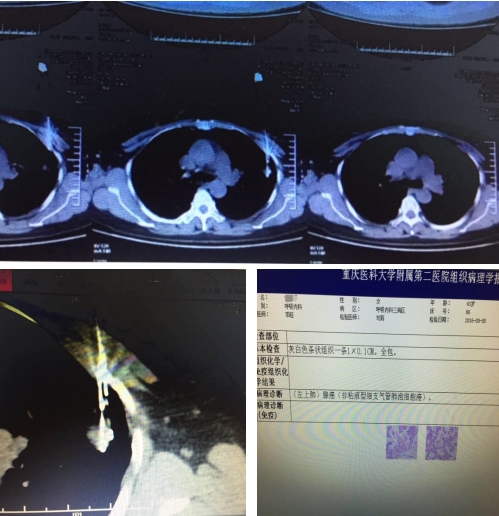

该女性患者发作性喘息多年,院外CT结果显示:左上肺0.8-1CM小结节。提示:不排除肺癌可能。肺癌在恶性肿瘤的死因中占首位,早期及时的诊断及治疗,对患者的预后效果、生存时间及质量,具有重大意义。CT引导下经皮肺穿刺活检,可以准确显示病灶本身情况及与周围组织结构的解剖关系。其病理诊断对治疗具有至关重要的作用。

结节病灶越小,离胸壁越远,定位越困难,越考验穿刺者的专业水准。该患者的病灶过于微小,目前国内也很少有能成功穿刺不足1CM病灶的病例。此次操作,需要操作者精准确定进针部位、角度及深度,稍有不慎,便易造成气胸、肺出血等并发症。经过胸部扫描,选取左侧胸壁穿刺点,并明确穿刺深度,李长毅副教授凭借10多年的临床经验,精湛的穿刺技术及耐心的操作,终于完成了这例操作难度较大,复杂程度高的穿刺手术。后组织病理学检查报告:左上肺腺癌(非粘液型细支气管肺泡细胞腺癌)。